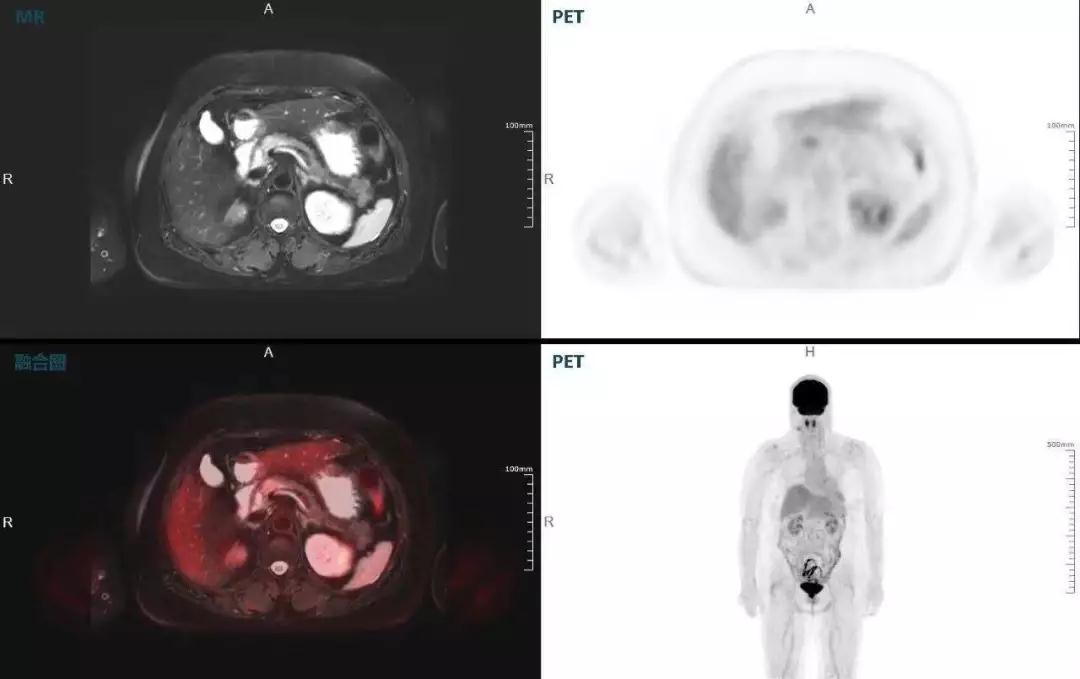

胰腺癌

中山醫(yī)院核醫(yī)學(xué)科在臨床實(shí)踐中發(fā)現(xiàn),基于聯(lián)影“時(shí)空一體”超清TOF PET/MR,不僅解剖信息和代謝信息能夠完美融合呈現(xiàn),同時(shí)精細(xì)展示局部病灶與周圍組織的復(fù)雜關(guān)系,并能全盤檢測病灶的全身轉(zhuǎn)移,為醫(yī)生臨床診斷提供更豐富信息。

(胰腺腫瘤,MR顯示胰腺體部信號(hào)異常,PET顯示稍高攝取,結(jié)構(gòu)改變和功能異常提示胰腺M(fèi)T可能大。)